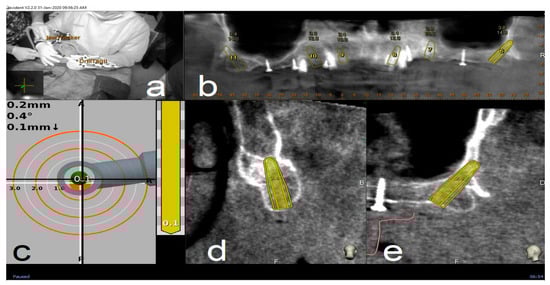

The preoperative surgical plan and the postoperative CBCT were superimposed using an accuracy evaluation software (EvaluNav™) part of Navident™ navigation system (Claronav Inc., Toronto, YTO, Canada). Calibration was done directly between the two volumetric images (Figure 8). Software provides various visualization tools that confirm two CBCTs are precisely matched. Once the user is satisfied with volumetric registration, the software automatically matches the planned implant shape onto the post-operative image and computes deviations between the planned and placed implant locations (Figure 9).

Figure 9.

The software automatically fits an implant model to its appearance in the post-operative image (a) and computes the angular axis corrected between the planned and actual implant locations (implant inserted with dynamic guidance) (b–d).